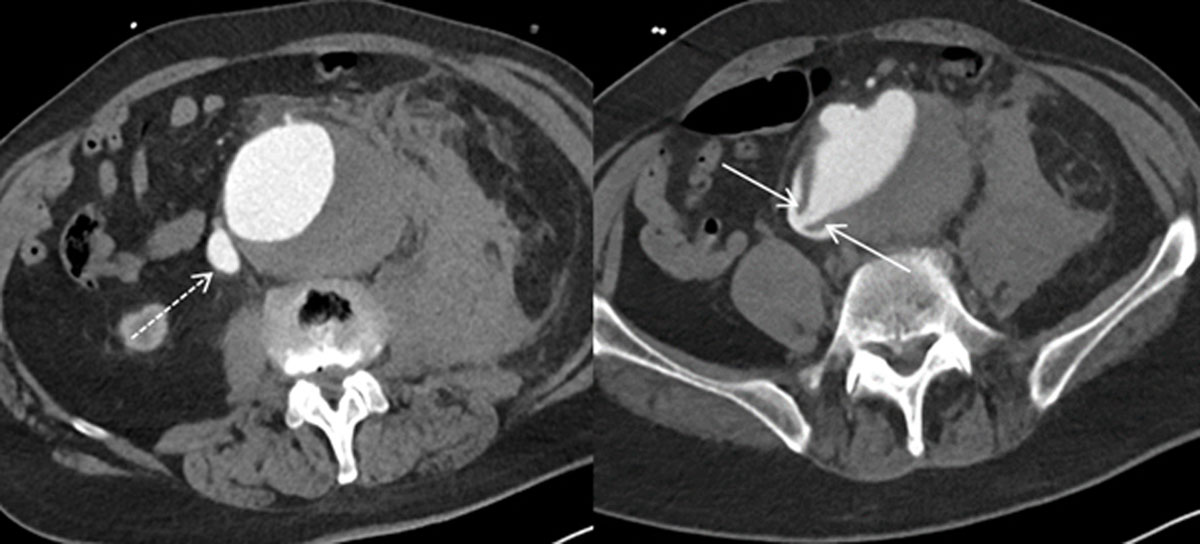

A multi-phase thoraco-abdominal computed tomography (CT) scan was requested. On CT, there was a large infrarenal aortic aneurysm up to 10 cm with a large para-aortic hematoma. Arterial phase opacification of the inferior vena cava and the common iliac vein, especially on the right side, was present (Figure 1, dashed arrow). Detailed study of the scan revealed a linear connection between the aorta aneurysm and the inferior vena cava (Figure 1, arrows), suggestive of an aortocaval fistula.

Figure 1